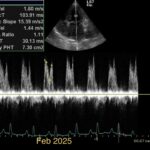

Chronic stage C MVD.TID Pimo and Lasix(high dose), ACEi and Spirono. Doing well. Recheck: Idexx GHP= CBC-NSF ,SDMA 15,BUN 14.1mmol/L, Creat 79umol/L. US: Cornell Indx LVd=1.46(prev2.1), LV septal flattening with diastolic dip,LAAO=2.47,Evel1.45m/s, TVregPG-68mmHg,HV distension-mod ascites.LV and LA underloading via diuretics and PHT (mild PHT past).PHT more pre vs post cap based on small LVsize? Consider Sildenafil/L Arg.Concerned about developing L CHF.Is CHF less likely adding PDE5i with MVD/PHT in underloaded LV than same scenario with vol overloaded LV at similar staging. MVPG=120.3mmHg

Thanks. Not sure if any sig. MV stenosis?? My experience limited.3 PWD from diff times. Ls7 vid. is from 2024,initially thinking reverse remodelling where the lasix lowering preload and Pimo is decreasing LV size via decreased resist/increase cxn while LA no change because it’s a chronic filled remodeled saggy bag receiving Regurge volume??